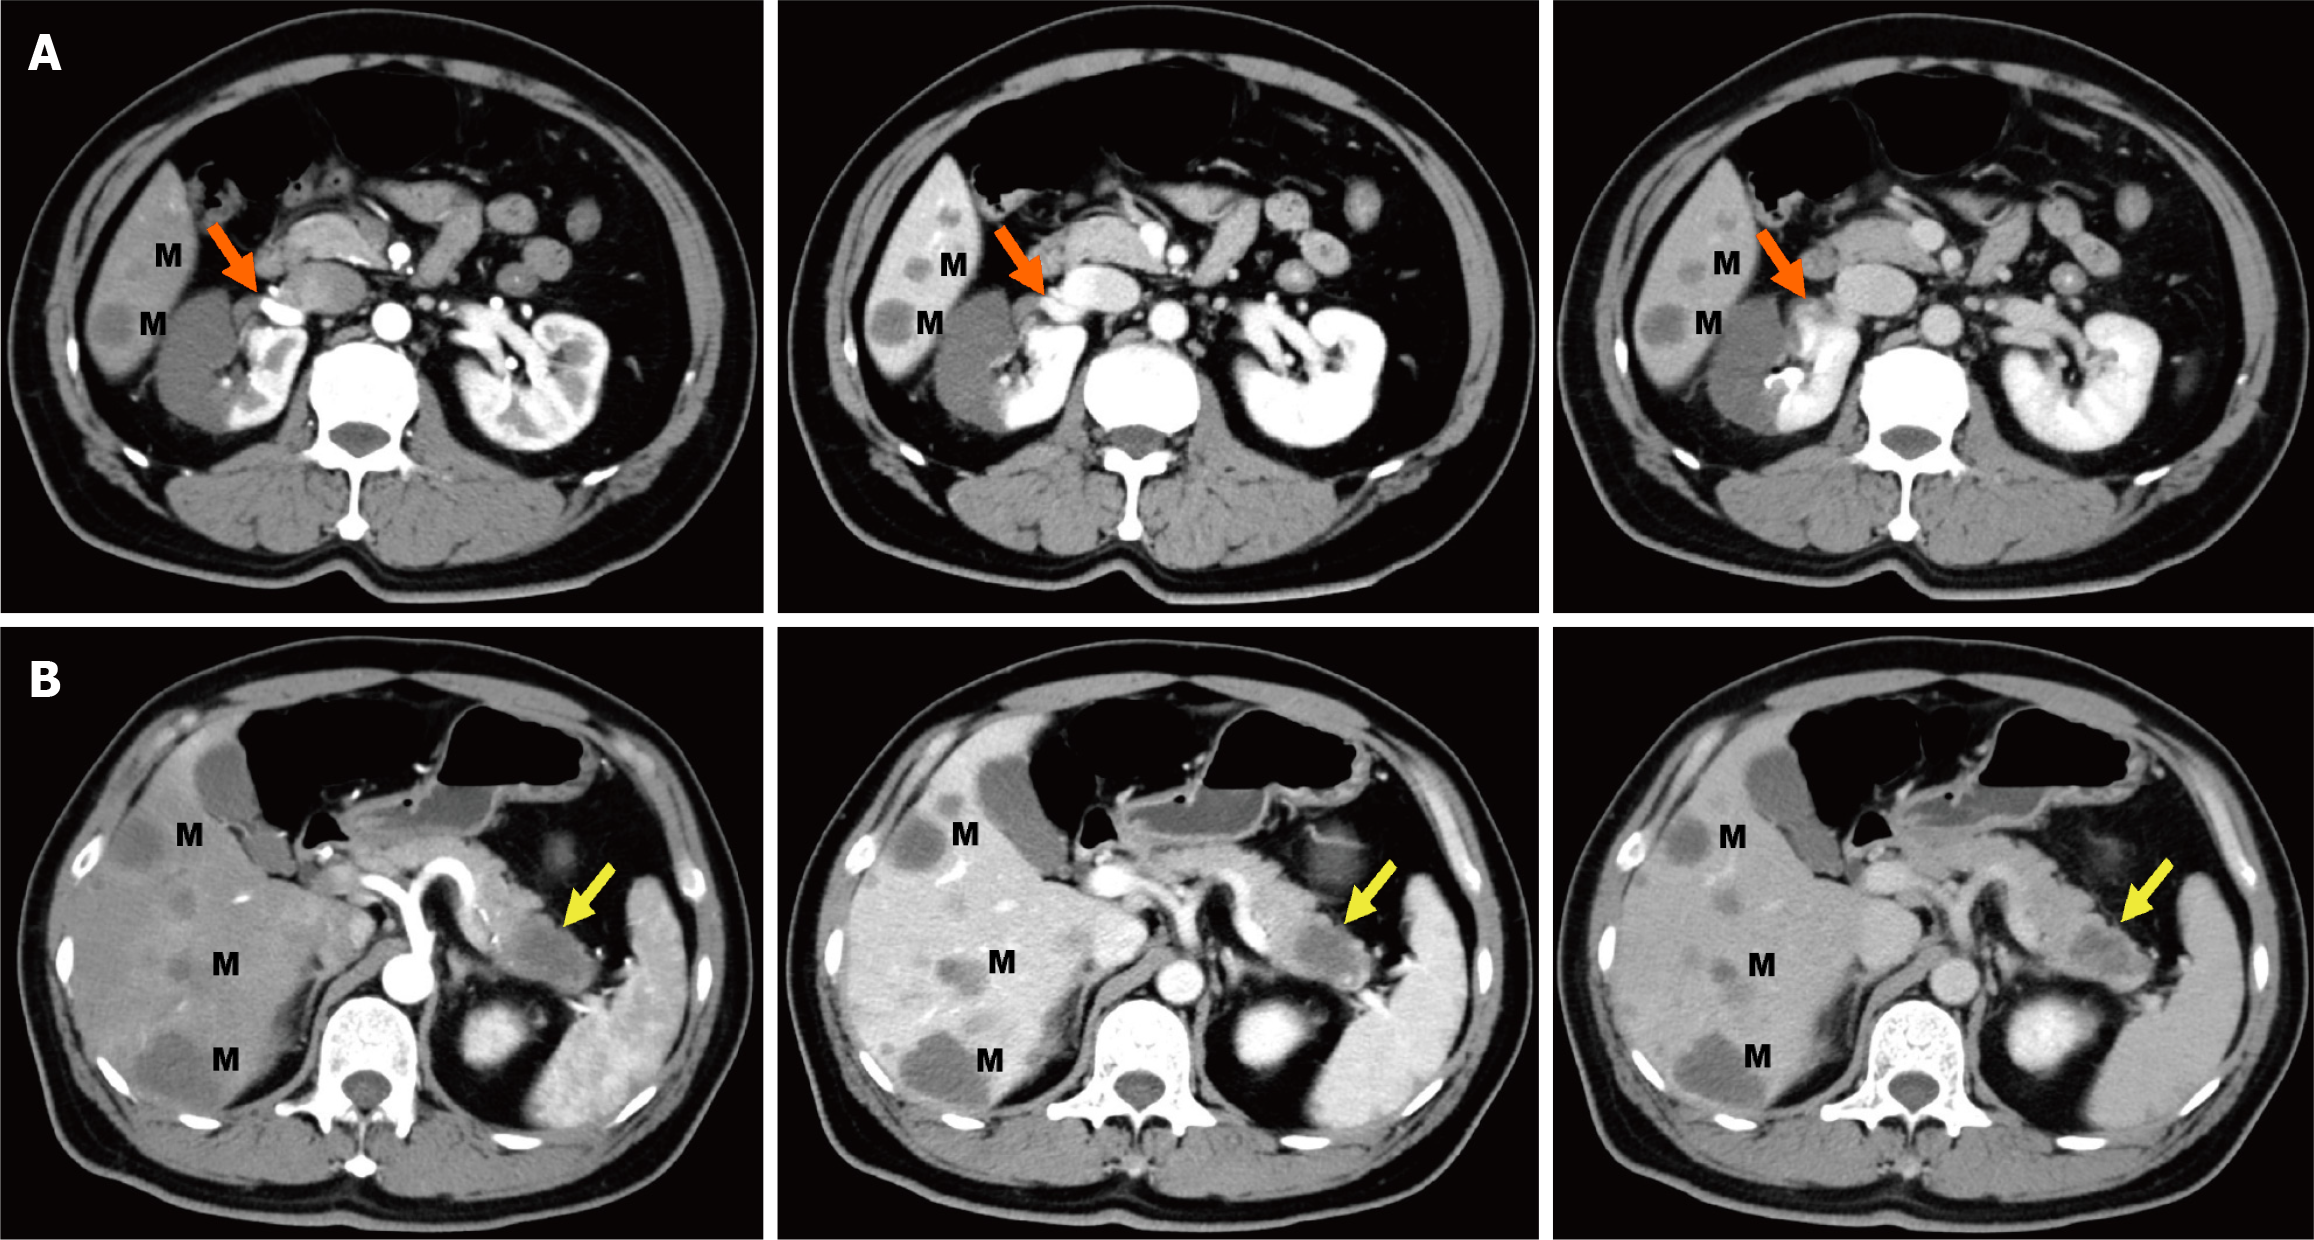

Combined with the discrepancy between the self-symptom and objective signs, we speculated on the possibility of thrombotic diseases and performed total abdominal CT angiography (CTA) and enhanced CT. The mesenteric artery CTA scan showed no significant abnormalities. However, a filling defect was visible in the anterior branch of the right renal artery, suggesting embolus formation, and the right kidney was abnormally enhanced (Figures 1A and 2A-D). Therefore, right renal infarction was diagnosed. Meanwhile, the abdominal CT suggested a soft tissue mass, approximately 4.0 cm × 2.6 cm in size, at the pancreatic tail with a poorly defined boundary, uneven internal density and liquefaction necrosis. On the enhanced scan, the lesion showed mild uneven enhancement, with a slightly high-density shadow in the sur